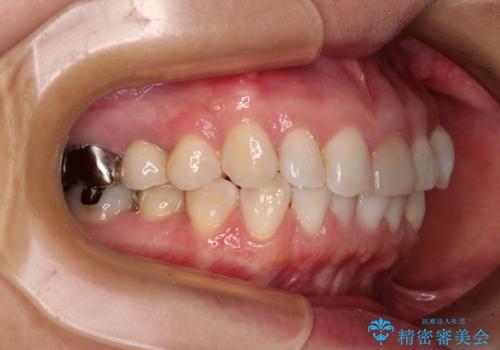

気になる下顎歯列のみをインビザラインで部分矯正

- 上下前歯のデコボコを気にして来院された患者様です。

カウンセリングにて詳しく話を聞いたところ、一番気になっているのは下顎前歯の叢生であり、上顎犬歯はあまり気になっていないとのことでした。

矯正治療は、歯の後戻りを抑制するために、治療終了後も保定装置をしっかりと使用していただくことが必須であるため、気になっている下顎だけを整えることで、その負担を半減できると考え、下顎のみの部分矯正として治療を行うこととしました。

装置としては、叢生の程度が強くなかったため、インビザラインの廉価版であるモデレート・パッケージを使用することとしました。

当院では治療前の歯列が整っていない限り、下顎前歯の舌側をワイヤーで固定するようにしています。下顎のみの部分矯正としたことで、マウスピース保定の負担を軽減することができました。

上顎は、失活して歯の色が変色しているため、将来的に補綴治療で自然な口元に仕上げていきたいとのことでした。